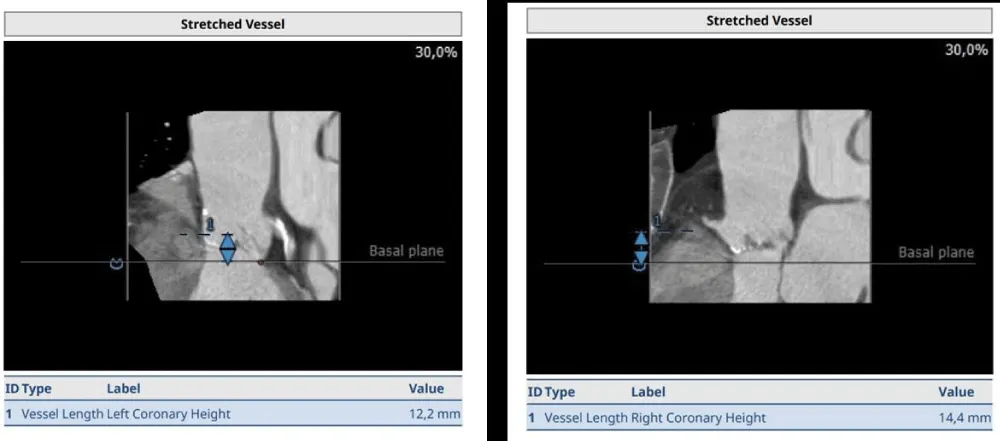

The clinical case concerns an 81-year-old woman with a history of systemic arterial hypertension, hypercholesterolemia, paroxysmal atrial fibrillation, chronic kidney disease, iron-deficiency anemia, and bilateral carotid atheromatosis for which she underwent a Carotid Endarterectomy (CEA) procedure. Additionally, she had a history of breast carcinoma, treated with surgery, subsequent chemotherapy, and ongoing Letrozole therapy. In 2019, the patient presented to the emergency department due to exertional dyspnea and low-threshold angina. During hospitalization, high average ventricular response (109 BPM) atrial fibrillation was diagnosed. Routine lab tests showed rising of hsTN-I (peak 800 pg/dL) and pro-BNP (peak 2476 pg/mL) and anemia Hb 9.1 g/dL. Echocardiography revealed severe depression of the left ventricular function (ejection fraction of 30%, with antero-apical akinesia) and low-flow-low-gradient aortic stenosis (mean gradient of 26 mmHg and AVAi of 0.5 cmq/m2 and SVi 29 mL/m2). So it was performed a Dobutamine stress Echo showed a rise of SVi up to 38 mL/m2 and a mean aortic gradient of up to 48 mmHg. Coronary angiography showed the right dominant coronary artery, of good caliber and course, with no angiographically significant lesions (Figure 1). The Left Main artery, with good caliber, had a 90% calcific stenosis at the distal segment, involving the proximal segment of the Left Anterior Descending artery. The Left Circumflex artery, with good caliber and course, presented a 30% ostial stenosis. The Intermediate Branch, with good caliber and course, showed 80% stenosis at the proximal segment (Figure 2). The Left Anterior Descending artery, also of good caliber and course, was diffusely atherosclerotic with a long, severely calcific 80% stenosis at the mid-distal segment (Figure 3). Therefore, the case was discussed by a multidisciplinary Heart team at our center. The STS score calculated indicated a mortality risk of 11.4%. Due to this high risk, surgical treatment was not considered, and the patient underwent a four-step percutaneous intervention. Before the intervention, a CT angiography was performed, revealing an aortic annulus area of 433.2 mm2, a perimeter of 75.3 mm, and a coronary height from the annulus of 10 mm. The right common femoral artery mean diameter was 6.1 mm2 and the external iliac artery was 8.4 mm2 with moderate tortuosity without significant calcification (Figure 4-6). Therefore, a 23 mm Edwards Sapien 3 valve was chosen. Our strategy consisted of 4 steps:

Figure 4: Before the intervention, a CT angiography was performed, revealing an aortic annulus area of 433.2 mm2, a perimeter of 75.3 mm, and a coronary height from the annulus of 10 mm. Therefore, a 23 mm Edwards Sapien 3 valve was chosen.